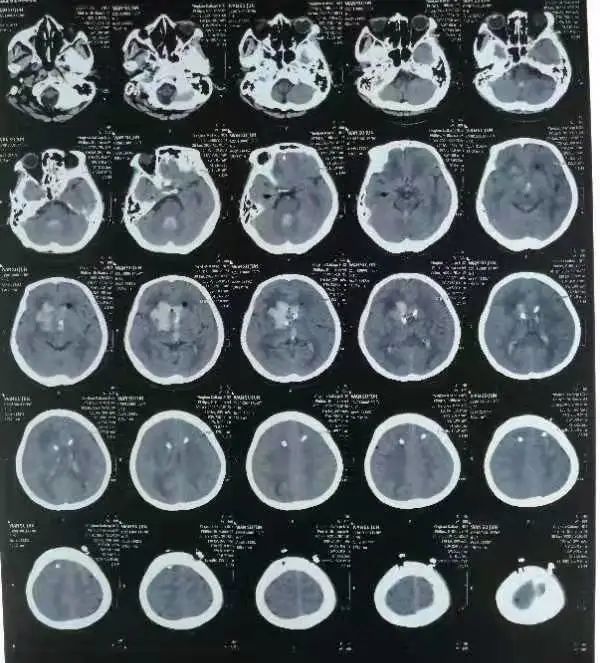

顺利打开脑室循环通路

经过前期充分的准备,手术很快开始。术中,吕松林主任凭借丰富经验,顺利将脑室引流管深入到了血肿关键位置。术后,在反复比对斟酌下,吕主任带领科室医护团队多次成功溶血后,顺利打开脑室循环通路。神经外科护理团队也紧跟治疗节奏,全程加强护理及预防,采用了多种护理方式纠正电解质紊乱、改善微循环,李奶奶终于转危为安。

(术前)